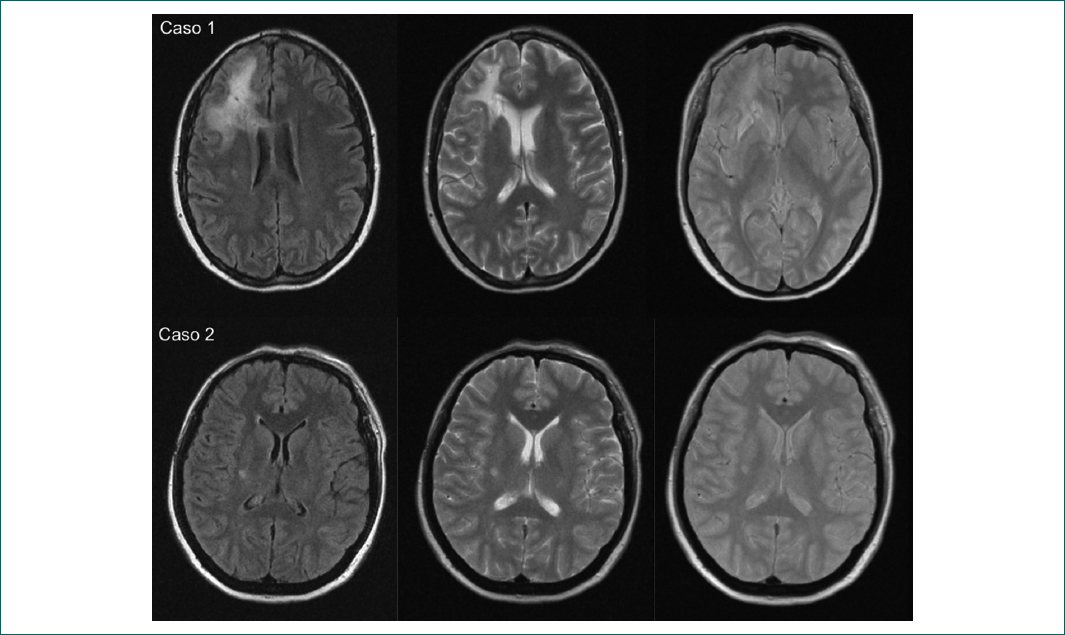

Mujer de 41 años cuyos síntomas comenzaron con atrofia supraciliar derecha, diagnosticada inicialmente como esclerosis en golpe de sable. Evolucionó con discromía y atrofia del tejido celular subcutáneo en la hemicara derecha, con extensión al hombro homolateral, y posteriormente presentó crisis convulsivas tónico-clónicas generalizadas y cefalea. La RM reportó datos compatibles con vasculitis del SNC (Fig. 1), que no se corroboró con una biopsia. La paciente presentó prueba de ANA con 1:160 (nucleolar) y luego 1:80 (moteado fino), anticuerpos anti-DNA y anticuerpos anticitoplasma de neutrófilos (ANCA) negativos, factor reumatoide 10.1 y proteína C reactiva de 11.3. Se concluyó diagnóstico de SPR. Se prescribió el uso de 1 g de ciclofosfamida (CFM), pero la paciente presentó leucocitopenia grave con la primera dosis, por lo que se cambió a azatioprina (AZT) a dosis de 1 mg/kg de peso (50 mg) y se logró el control de la enfermedad luego de 1 año de tratamiento. Se realizó injerto graso en la frente, el mentón y el hombro con cirugía plástica; además, la paciente requirió tratamiento anticonvulsivante. En el seguimiento, la paciente se encuentra con control de crisis convulsivas, sin cefalea y sin deterioro neurológico, aunque persiste el tratamiento con AZT.

Mujer de 43 años cuyos síntomas iniciaron a los 8 años, después de un traumatismo craneoencefálico. La paciente presentó dermatosis no especificada en la región parietal derecha, la cual progresó con alopecia, atrofia y deformación ósea hasta el área supraciliar homolateral. A los 19 años de edad presentó parálisis facial periférica homolateral y requirió blefaroplastia en tres ocasiones. A los 27 años de edad se le realizó rinoplastia. Cursó con trastorno depresivo mayor, que requirió tratamiento con paroxetina por 3 años, y cefalea de características migrañosas (unilateral, derecha, duración > 5 horas, acompañada de fotofobia, náusea y vértigo). A los 40 años de edad se confirmó el diagnóstico de SPR por la evolución y una biopsia con reporte de fibrosis intersticial y perivascular en la dermis, con ausencia de folículos pilosos, reportada como esclerosis localizada. La TC reportó hemiatrofia parenquimatosa cerebral derecha y la RM mostró imágenes compatibles con vasculitis del SNC homolateral (Fig. 1), no corroborada por la biopsia. En este caso no se realizó EEG por no haber crisis convulsivas. La prueba de ANA reportó 1:160 (moteado fino), los anticuerpos anti-DNA y ANCA fueron negativos, el factor reumatoide 0.8 y la proteína C reactiva 3.28. La paciente recibió tratamiento con metilprednisolona (MPD), seguida de CFM (1 g mensual durante 6 meses y posteriormente bimensual por 12 dosis), con respuesta después de 1 año de tratamiento.